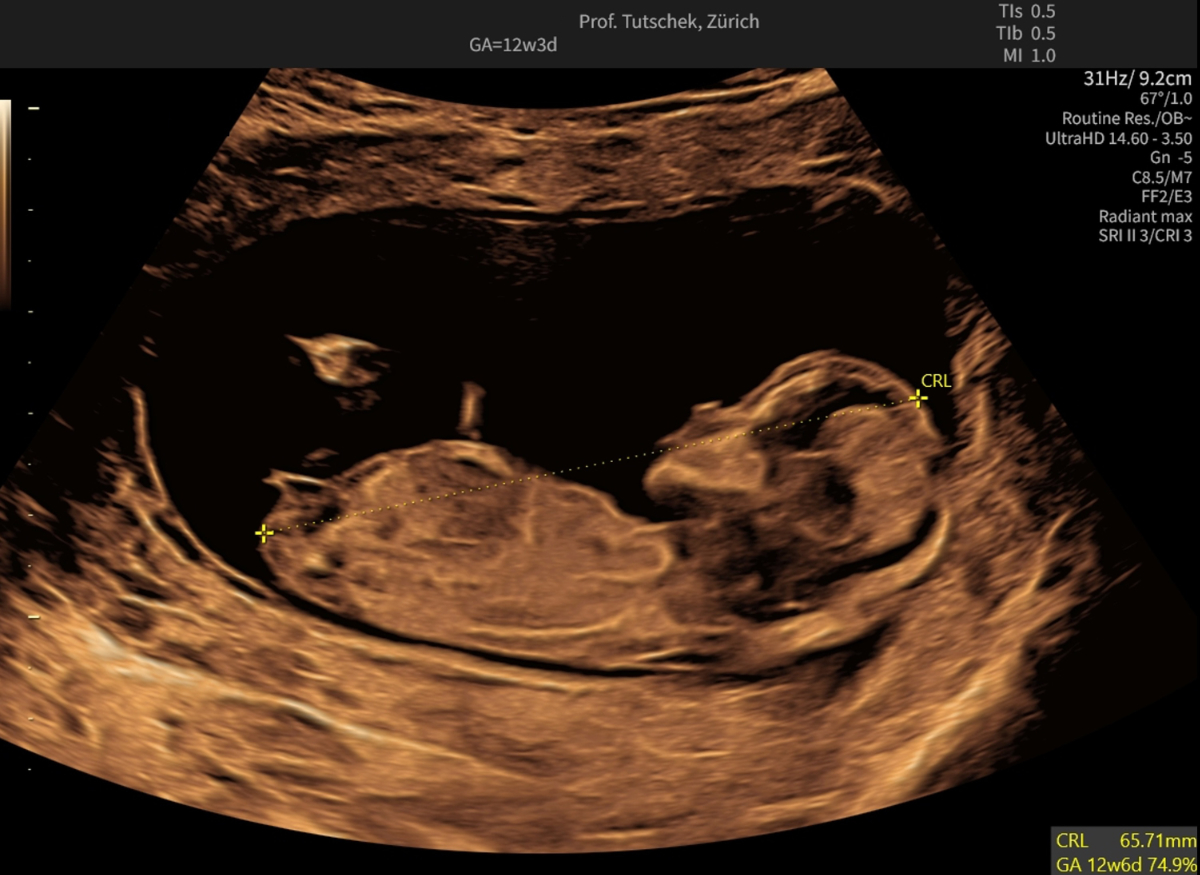

Ultrasound (US) and blood parameters show characteristic deviations in pregnancies complicated by fetal trisomy 21, trisomy 13 and trisomy 18 as well as in many other pathological conditions. Two of three foetuses with trisomy 21 show an increased nuchal translucency (figure 1a-c).

Figure 1aUltrasound measurements during the first trimester ultrasound: measurement of the crown-rump length (CRL) (65.71 mm).

To achieve a trisomy 21 detection rate of 85%, free beta-hCG and PAPP-A must be added in a quality-controlled fashion and using a certified algorithm. In trisomy 21, free beta-hCG is elevated and PAPP-A decreased (figure 2). The combined test (first trimester screening [FTS], called Ersttrimestertest in Switzerland) combines these two biomarkers with morphological parameters obtained by US, ideally done between 12 and 13 weeks (60–70 mm crown-rump length [CRL]).